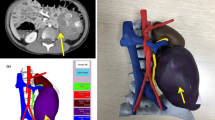

Class 2. Developing classification (33.8%) helped clinicians with two important functions: (1) determining the appropriateness of a specific diagnosis or intervention9,17,24,27,28,33,35,36,40,54,57,59,66,71,74,76,90,98,99,103,104,106,107,108,111,112,117,119,120,123,126,134,137,139,142,143,144,145 (termed Decision, 15.7% of all patients), or (2) practicing a given procedure on a patient-specific replica20,25,41,46,51,58,73,78,85,91,93,97,105,113,114,116,128,131,138,141 (termed Simulation, 18.1% of all patients), both for surgical operations and other procedures such as cardiac catheterizations. At times, decision models revealed that a procedure was unnecessary or unlikely to improve a patient’s condition. In one example, a 3DP model of a complex ventricular septal defect, initially imaged with echocardiogram and CT, allowed the clinician better visualization of the defect and driving the decision not to operate and sparing the child considerable morbidity.111 Simulation models also aimed to reduce morbidity by increasing precision of complex surgeries; for example, 3DP was used to accurately simulate a laparoscopic adrenalectomy for neuroblastoma complete with 3DP renderings of the tumor, the surrounding anatomy and even the outer abdominal cavity.141 Developing applications were used most commonly for central nervous system applications, particularly in planning for spinal surgery (30.3% of all patients).

Souzaki, R. et al. Three-dimensional liver model based on preoperative CT images as a tool to assist in surgical planning for hepatoblastoma in a child. Pediatr. Surg. Int. 31, 593–596 (2015).

Souzaki, R. et al. Preoperative surgical simulation of laparoscopic adrenalectomy for neuroblastoma using a three-dimensional printed model based on preoperative CT images. J. Pediatr. Surg. 50, 2112–2115 (2015).